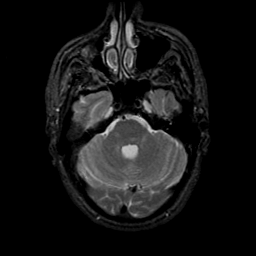

MR Study #9, April 14, 1991 -- Slice #13